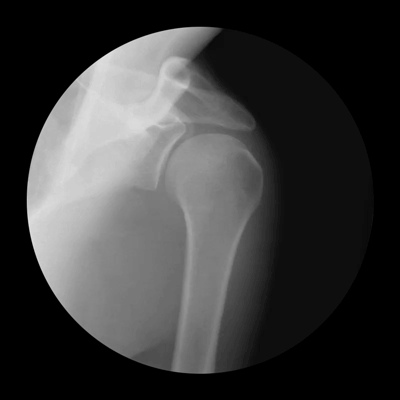

Плечевой сустав — типичный шаровидный сустав, образованный головкой плечевой кости и суставной впадиной лопатки. Суставная впадина лопатки представляет собой уплощенную ямку в форме груши или перевернутой запятой с поверхностью, приблизительно в 4 раза меньшей поверхности головки плечевой кости. Головка плечевой кости повернута примерно на 30° назад от поперечной оси локтевого сустава, а лопатка повернута на такой же угол вперед от фронтальной плоскости тела; таким образом, головка плечевой кости и суставная впадина лопатки обращены ровно друг на друга. Во время движений в плечевом суставе лопатка вращается, обращая свою суставную впадину вверх, вниз, наружу или внутрь, благодаря чему центр головки плечевой кости продолжает оставаться внутри нее. Когда же такое центрированное положение головки плечевой кости в суставной впадине нарушается, возникает опасность вывиха в плечевом суставе.

Биомеханика плечевого сустава на рентгене